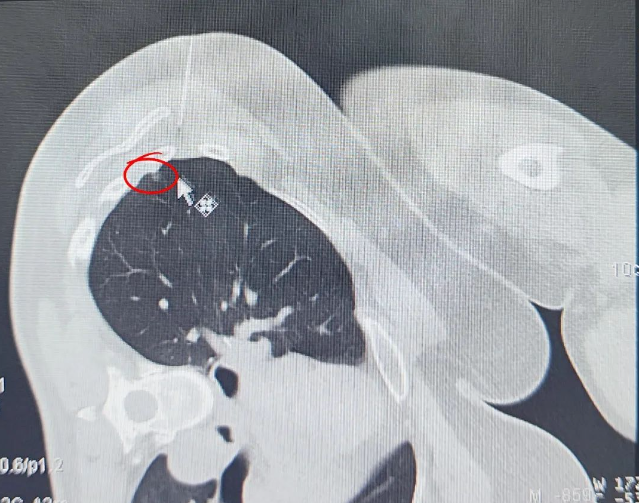

定位技術(shù)升級(jí)通過(guò) CT 影像精準(zhǔn)鎖定 6mm 磨玻璃結(jié)節(jié)(圖示可見(jiàn)),全程在麻醉狀態(tài)下完成定位操作,顯著降低傳統(tǒng)清醒定位可能引發(fā)的患者緊張情緒及轉(zhuǎn)運(yùn)風(fēng)險(xiǎn)。微創(chuàng)技術(shù)突破運(yùn)用精細(xì)化微創(chuàng)操作分離粘連組織,在切除病灶過(guò)程中精準(zhǔn)避讓正常肺組織,經(jīng)術(shù)后影像評(píng)估,實(shí)現(xiàn)病灶完整清除與健康肺功能保留的平衡。